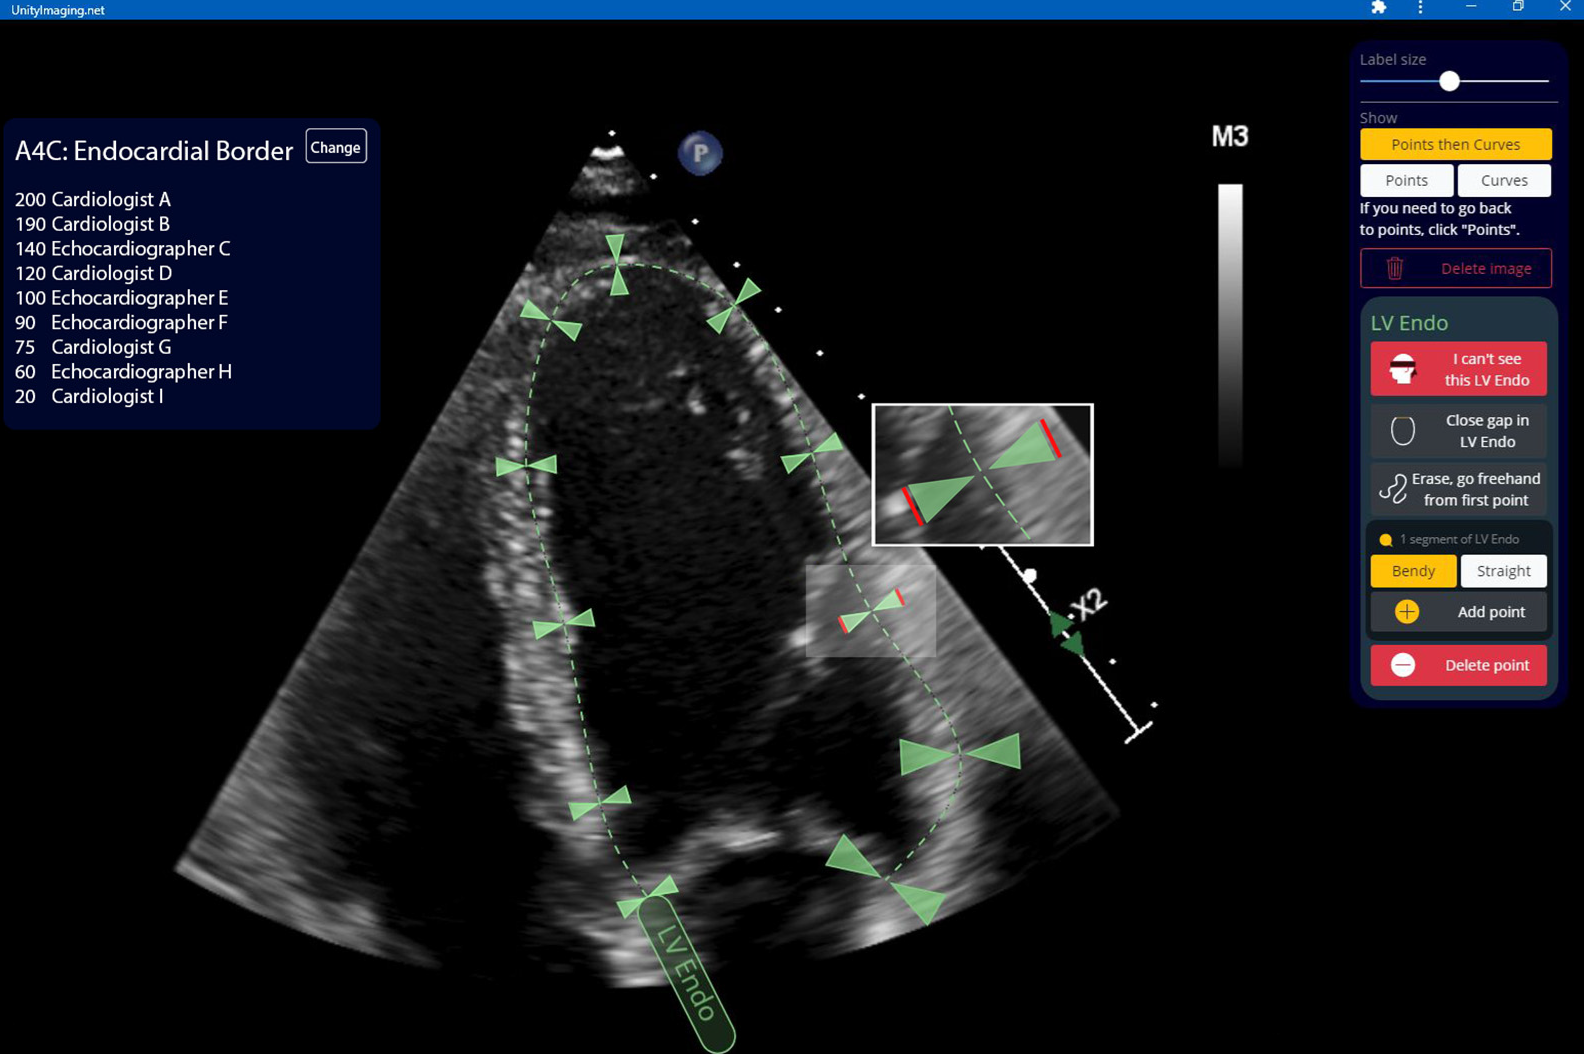

The annotation of this dataset was facilitated using https://data.unityimaging.net.

The Unity web-based, interactive, real-time annotation platform enables clinical experts across the UK to collaboratively and efficiently label medical images. The platform’s intuitive interface allows experts to annotate key anatomical structures with precision, including critical features such as key points and curves along the endocardial border, as illustrated above. The platform’s accessibility and real-time capabilities facilitate large-scale multi-expert annotations, enhancing the quality and accuracy of labelled datasets for medical image analysis.